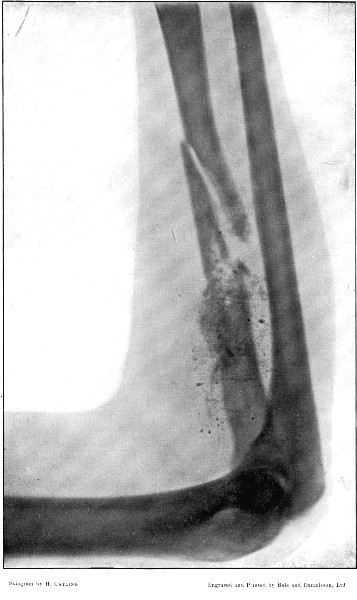

3. Punctured Fracture of Clavicle162

4. Comminuted Fracture of Shaft of Humerus180

5. Comminuted Fracture of Humerus accompanied by an Explosive Exit182

6. Comminuted Fracture of Humerus due to Oblique Impact184

7. Same Fracture healed186

8. Low Velocity Fracture of Humerus With Retained Bullet188